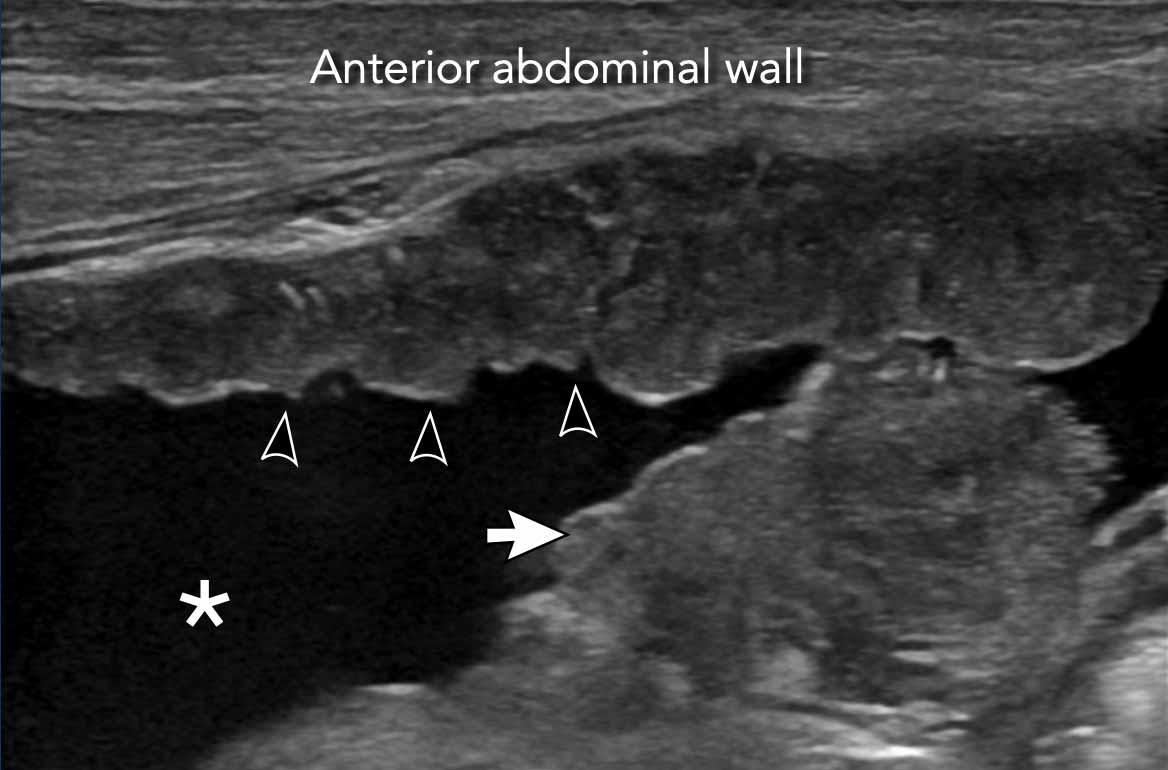

Hình ảnh

Hình ảnh siêu âm của một bệnh nhân nhập viện với cổ trướng (dấu hoa thị) cho thấy cả các nốt khối u trên phúc mạc thành (đầu mũi tên) lẫn một khối u lớn trên phúc mạc tạng (mũi tên trắng).